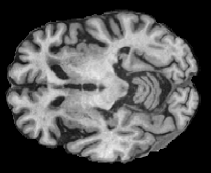

In order to analyze qualitatively the results of our generator, we extract slices with different WMHs loads, Table 4 shows the reconstruction results for three different levels of loads. As we can see in the first row, both methods produce a similar response in regions with a low load of lesions, it can be observed that generated images are similar to the real FLAIR images in the left, and these not present evident structural distortions. However, it can be noted images exhibit blurred effects, which can be due to L2 based optimization, more complex generative networks with adversarial loss optimization as GANs tend to eliminate blurred effect but at the expense to produce structural distortions. In the application presented in this work it is important to preserve the structural information, thus, our L2 based optimization present a good balance between preserve structural information and blurred effects. In the second and third column, it can be observed the performance of both methods when facing the presence of lesions, as can be seen, both methods have a good response to large and contiguous lesions. It also can be noted both methods tend to produce poor performance in small and diffuse WMHs marked in red, note, these lesion do not exhibit identifiable patterns in T1 images, however it can be seen that our proposed method is more sensitive to these patterns which enable to highlight some small regions as those marked in green.

FLAIR T1 Offline synthesis Proposal

[Uncaptioned image] [Uncaptioned image] [Uncaptioned image] [Uncaptioned image]

Table 4: Results of Generation for all the proposed methods,